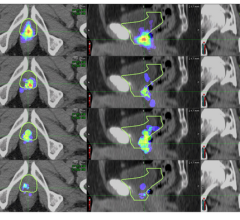

June 26, 2023 — A first-in-human evaluation of the novel theranostic pair 68Ga-DOTA-5G / 177Lu-DOTA-ABM-5G has confirmed ...